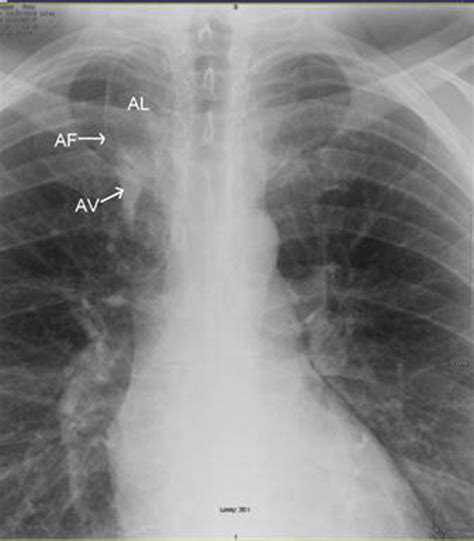

The hallmark of the Vena Azygos Lobe on a chest radiograph is a characteristic curvilinear density. Because of its unique formation, it is easily identifiable if one knows what to look for. Clinicians and radiologists typically identify the following features:

• The Azygos Fissure Line: A thin, convex line extending from the apex of the right lung toward the hilum.

• The Azygos Point (or Teardrop): A dense, teardrop-shaped opacity at the inferior end of the fissure line. This represents the cross-section of the misplaced azygos vein itself.

• Location: Always found in the right upper lobe.